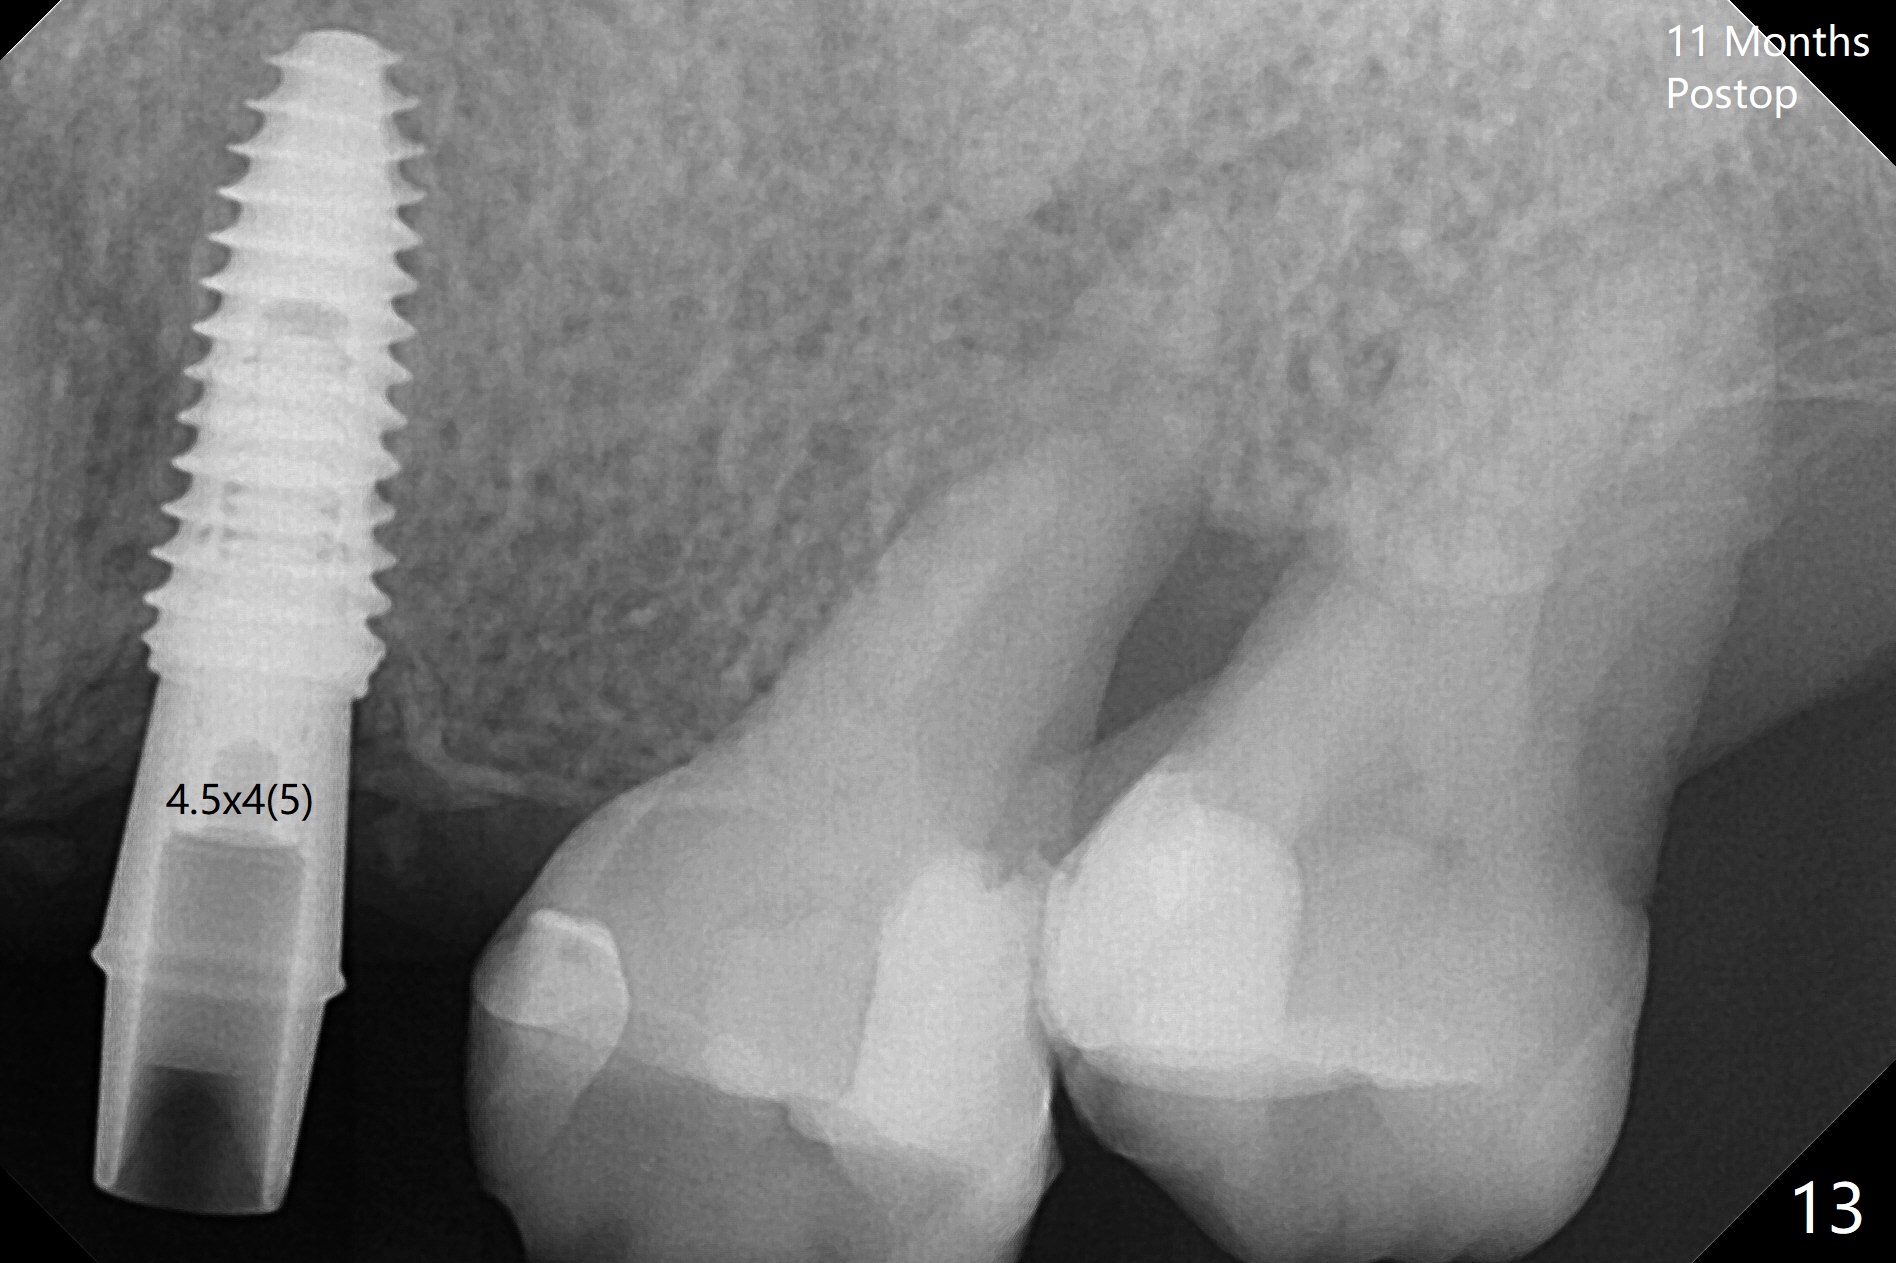

PA is taken after a 2.2 mm drill reaches the depth at #12, since osteotomy is initiated in the mesial slope of the socket (Fig.1 red dashed line) and the neighboring root (*) slightly curves distal. A 8.6x5 mm healing abutment is used to close the socket with the large mesiodistal space after bone graft (Fig.2 *). In contrast, the socket at #20 is large; a 4.5x4.5(3) mm cementation abutment is placed for an immediate provisional to keep autogenous bone (harvested from the site of #18) in place (Fig.3). Six months postop, the patient does not want implant FPD. She wants an additional implant at #19. Since the space between the implants #18 and 20 is 9.41 mm, a narrow implant is indicated (3 or 3.5 mm, Fig.4), in spite of the sufficient buccolingual width (Fig.5). The position and trajectory of the 1.2 mm initial drill and 3x10(2) mm 1-piece implant are acceptable with free hand (Fig.6,7). After 3-4 more turns, panoramic X-ray (Fig.8) and CT (Fig.9) are taken for 28-30 guide. It appears that the 1-piece implant is placed acceptable buccolingual (Fig.9 B). The implants at #12,18,20 (4.5 months postop with guide) are shown in Fig.10-12. It appears that guided surgery is superior in buccolingual position and trajectory to free hand. There is crestal remodeling without implant thread exposure 11 months postop (Fig.13).